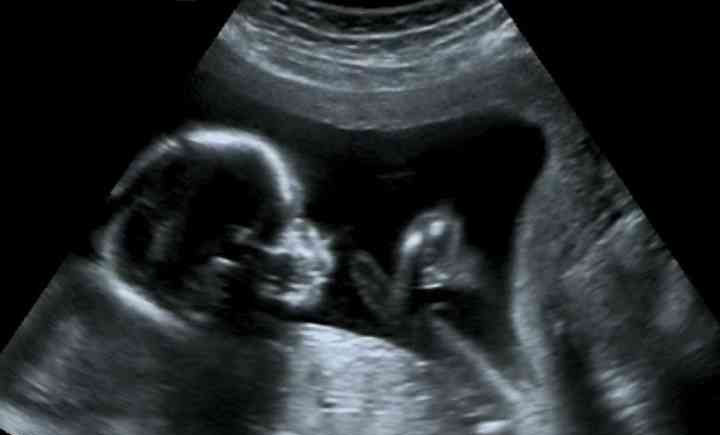

辨别胎儿性别的办法是非常多的,最常见的就是酸儿辣女、肚子形状、胎儿心率等辨别方法,但是这些辨别方法并没有足够的科学依据,目前所能知道胎儿性别比较准确的方法就是通过唐氏筛查的数据来进行判断,最准确的方法是四维彩超,但是在孩子出生前医生是不允许透露孩子性别的。

这种方法的准确率并不能达到100%,但是是有科学依据的,最准确的方法还是四维彩超,但是在孩子剩下来之前医生是不允许告知孩子性别的,所以这种方法行不通。